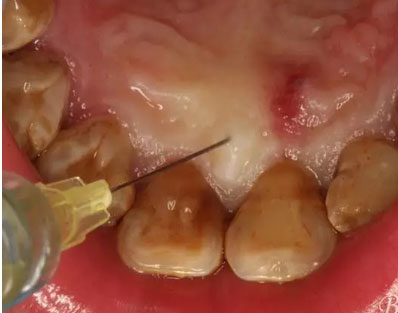

圖5.唇側(cè)局部無(wú)痛浸潤(rùn)麻醉